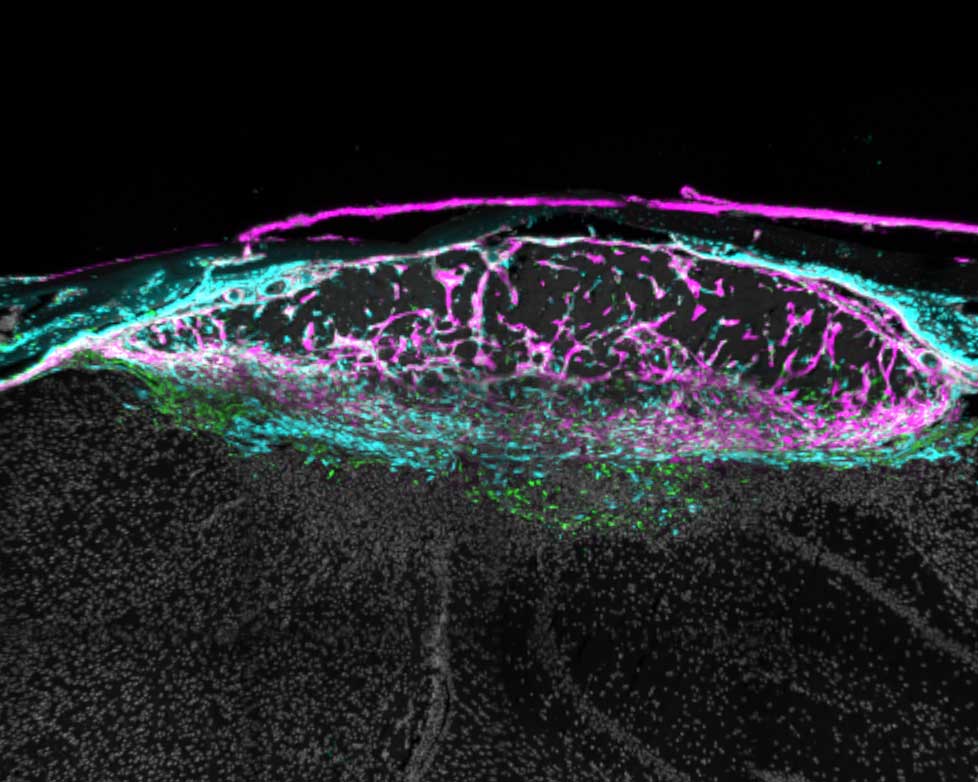

Various views of a mouse brain cortex seven days after a stroke that caused injury. Green dots show fibroblast cells; pink areas show collagen produced by the fibroblasts to create a protective scar layer; and blue shows blood vessels with fibroblasts. All images by Molofsky Lab, UCSF

A mouse brain cortex seven days after a stroke that caused injury. Fibroblasts (green) have created collagen (pink) to form a protective scar layer around the injury.